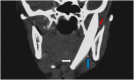

Case presentation: A nine year-old patient presented with a limited mouth opening (0.5 cm). Initial examination showed a scar of an old trauma in the submandibular area two months prior to presentation. The radiographic study showed a large knife-shaped foreign body with its tip at the infra-temporal region, and its base at the submandibular region. Further multi-slice computed tomography with angiography was done that showed close proximity of the foreign body to the branches of the external carotid artery; maxillary, lingual and facial branches. The foreign body was removed via extra-oral approach through the old scar of the past injury under general anesthesia. Dissection, exposure of the external carotid artery and preparing it for emergency ligation, were done before extraction of the foreign body. The patient's mouth opening increased to 2.5 cm without any complications.